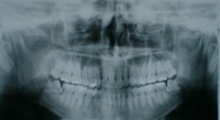

しかし、アゴの骨が小さく、はえる場所が狭いとななめに向いてはえてきたり、骨の中にもぐった状態のままで一生はえてこない場合も多く、このような骨の中にもぐったままの状態の歯を埋伏歯(まいふくし)と言います。

骨にもぐった状態の親知らずの抜歯は通常の抜歯に比べると難易度が高く熟練された技術が必要となります。

■抜歯の方法

下アゴの埋まった状態の親知らずを例にあげますと、まず親知らずの周囲の歯ぐきの粘膜に局所麻酔注射をして痛みをとります。

そして、粘膜を切開して骨を露出させ必要に応じて骨を削ります。

埋まっている智歯を2~3個に分割して摘出した後、洗浄して粘膜を元の状態に戻し、縫って終了です。

抜歯に要する時間はおおよそ20分~30分くらいです。